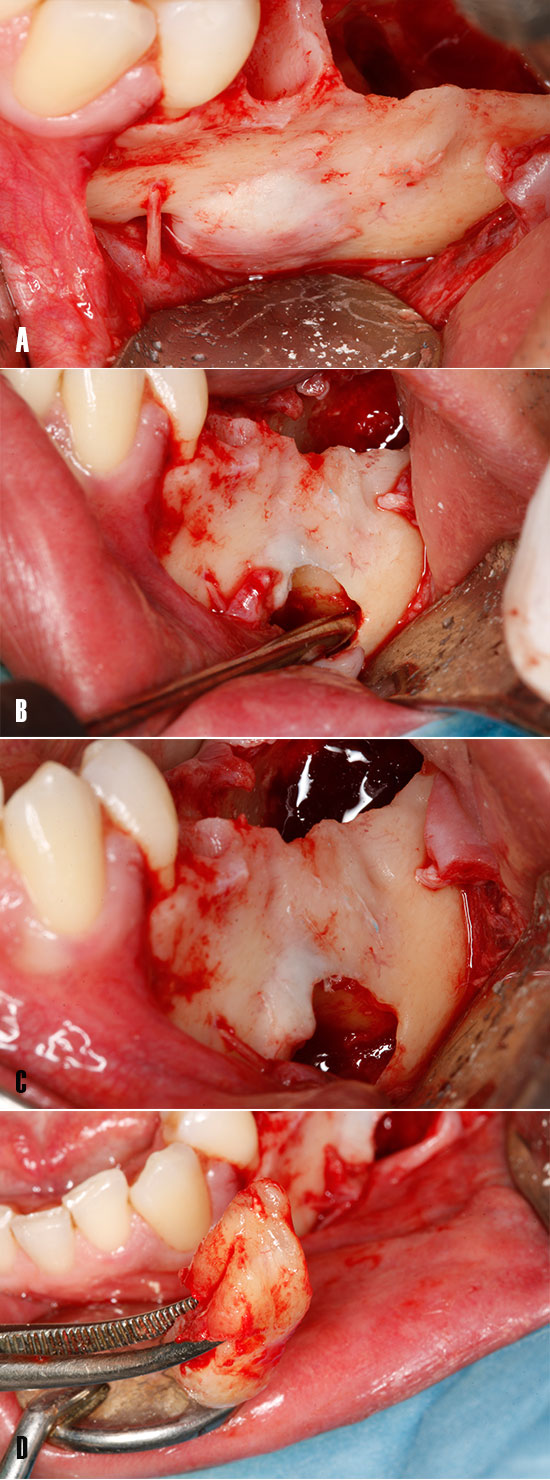

La cirugía se realizó bajo anestesia local infiltrativa y troncular del nervio dentario inferior izquierdo con Articaína al 4% (1:100,000) (Inibsa; Lliça de Vall, Barcelona, Spain). Se realizó una incisión a espesor completo con una hoja bisturí 15c, para elevar un colgajo mucoperióstico. Tras la elevación del colgajo, antes de acceder a la cavidad quística, se procedió a la extracción de los dientes afectados por la rizólisis (Fig.5), así como del tejido membrana fibrosa del proceso quístico (Fig. 5C).

Figura 5. Enucleación del quiste. A) Elevación de colgajo mucoperióstico. B) Extracción del diente 3.6 afectado por la rizólisis debido al proceso osteolítico. C) Se procede a enuclear la parte más superficial de la lesión. D) Dientes 3.5 y 3.6 tras la extracción.

Tras enuclear el tejido inflamatorio, se pudo observar los dientes impactados relacionados al quiste dentígero, y que fueron extraídos previa odontosección de la porción coronaria empleando fresas de carburo tungsteno (Jota AG, Rüthi SG, Switzerland) empleando una pieza de mano recta 1:1 (Synea Vision, W&H Dentalwerk, Bürmoos, Austria) (Fig. 6).

Figura 6. Extracción de los dientes impactados. Imagen intraoral - vista oclusal. A) Tras las extracción de los dientes afectados por la rizólisis y posterior enucleación del quiste, se pudo visualizar los dientes impactados que causaron la patología. B) Se procede a realizar la odontosección de la porción coronal. C) Extracción de los fragmentos coronales tras la odontosección.

Para la extracción de las porción radicular del diente 3.7, se realizó la ostectomía de la cortical vestibular creando una pequeña ventana de acceso, mediante la cual se insertó un elevador recto (Fig.7).

Figura 7. Extracción de los dientes impactados. Imagen intraoral – vista lateral. A) Nótese el ensanchamiento de la cortical vestibular y proximidad de la emergencia del nervio mentoniano. B) Se realiza una ostectomía a manera de ventana, para así acceder a la porción radicular del diente 3.6 para su extracción con ayuda de un elevador recto. C) El diente 3.6 ha sido desplazado. D) Diente fuera de boca tras su extracción.